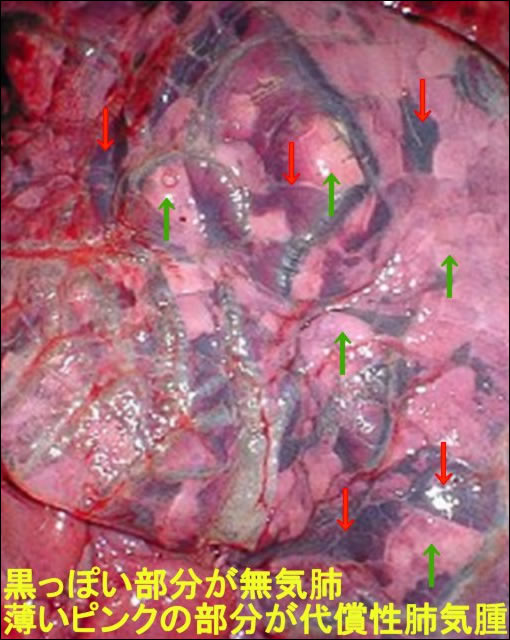

時々「子牛がミルクを引っかけた」とか、「竹づっぽ(竹筒)で薬を飲ませたらのどに入ってしまった」などの稟告で急診がくることがあります。いわゆる誤嚥性肺炎(誤飲性肺炎とか吸飲性肺炎ともいいます)というやつです。 これが以外とやっかいなのです。最初はそんなに悪くなさそうだったのに、時間がたつごとに苦しそうになってきて、最後は倒れて死んでしまった、なんて例もあります。 どうしてそんなことになるのかというと、上の図のように、はじめは薬やミルクなどを引っかけたところだけが悪いのですが、その分呼吸が苦しいので、ほかの部分ががんばって呼吸しすぎて、一部はパンパンに空気がたまって吐き出せない状態(代償性肺気腫といいます。)になります。そうなるとさらに酸素を吸収する部分が少ないから、またほかの健康な部分ががんばりすぎて肺気腫になって..。と悪循環を繰り返し、肺のガス交換(酸素を取り入れて二酸化炭素を排出する働き)が働かなくなって最後は死んでしまうのです。 ですから、まず誤嚥をさせてしまったときは、落ち着いて牛さんに運動制限をかけます。追いかけ回したりすると、体が酸素を要求するので大きな呼吸をするため、よけいに肺気腫部分が増えちゃうんですね。もしも同居牛がいる場合は、同居牛をほかの部屋に移して、誤嚥下牛の安静を確保した上で獣医さんを呼んでくさい。なにせ、肺に引っかけたのがミルクとか薬ですから、ばい菌の繁殖にも好都合です。最初にきちんと処置してもらった方がよいのです。それから、予後判定(これから回復するのか、進行するのかの判断)は、誤嚥後15分から1時間は状態を観察するべきです。 |